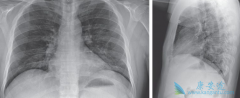

近日,美国首例新型冠状病毒(COVID-19)患者在服用抗病毒药瑞德西韦 ( Remdesivir )后症状得到了显著改善的消息受到了人们的广泛关注。瑞德西韦由美国吉利德公司开发,起初的研发目的是用于防治埃博拉病毒感染,而目前被证明对于新冠病毒有立竿见影的疗 ...